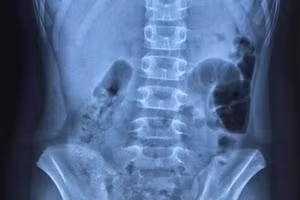

GD&TĐ - Bệnh viện Đa khoa tỉnh Thanh Hóa thực hiện thành công ca nội soi gắp dị vật sắc nhọn xuyên thủng thành dạ dày vào ổ bụng cho bệnh nhân nữ 79 tuổi.